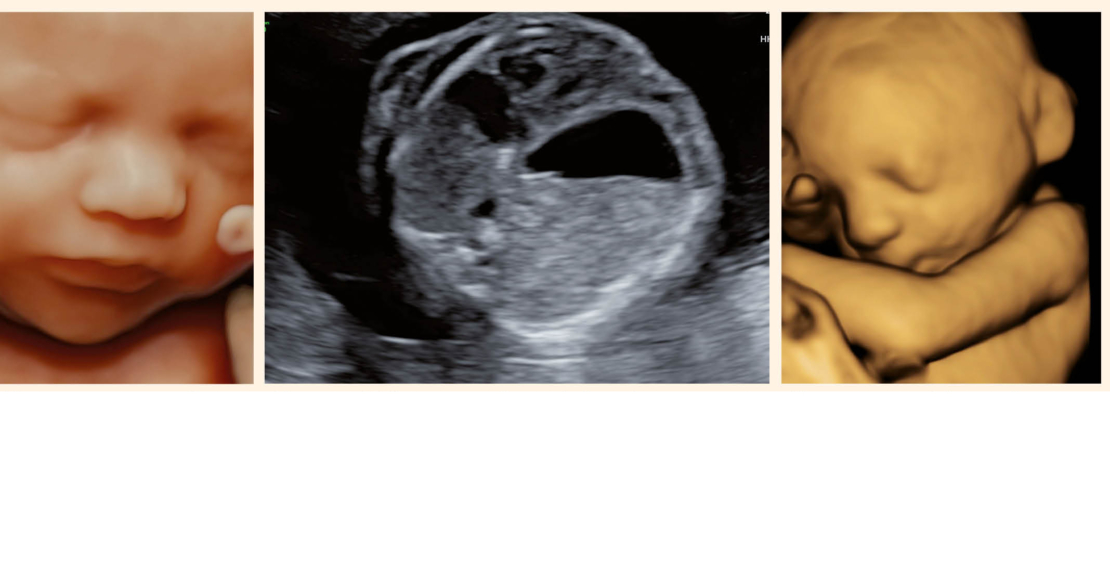

Fetale Ursachen die zu einer gestörten Fruchtwasserzirkulation führen sind vielfältig: Neben den intrauterinen Infektionen, kommen auch fetale Anämien mit immunologischem Hydrops, Chromosomenstörungen, neuromuskuläre Erkrankungen und verschiedene strukturelle Fehlbildungen in Betracht (Tab. 2). Vor allem wenn eine Kombination von Polyhydramnion und fetaler Wachstumsretardierung vorliegt sollte eine fetale Fehlbildung ausgeschlossen und eine Karyotypisierung angeboten werden.

Vorteilhaft und hilfreich für die detaillierte Ultraschalldiagnostik ist die häufig sehr gute Darstellbarkeit bei gutem Ultraschallfenster (Abb. 4).